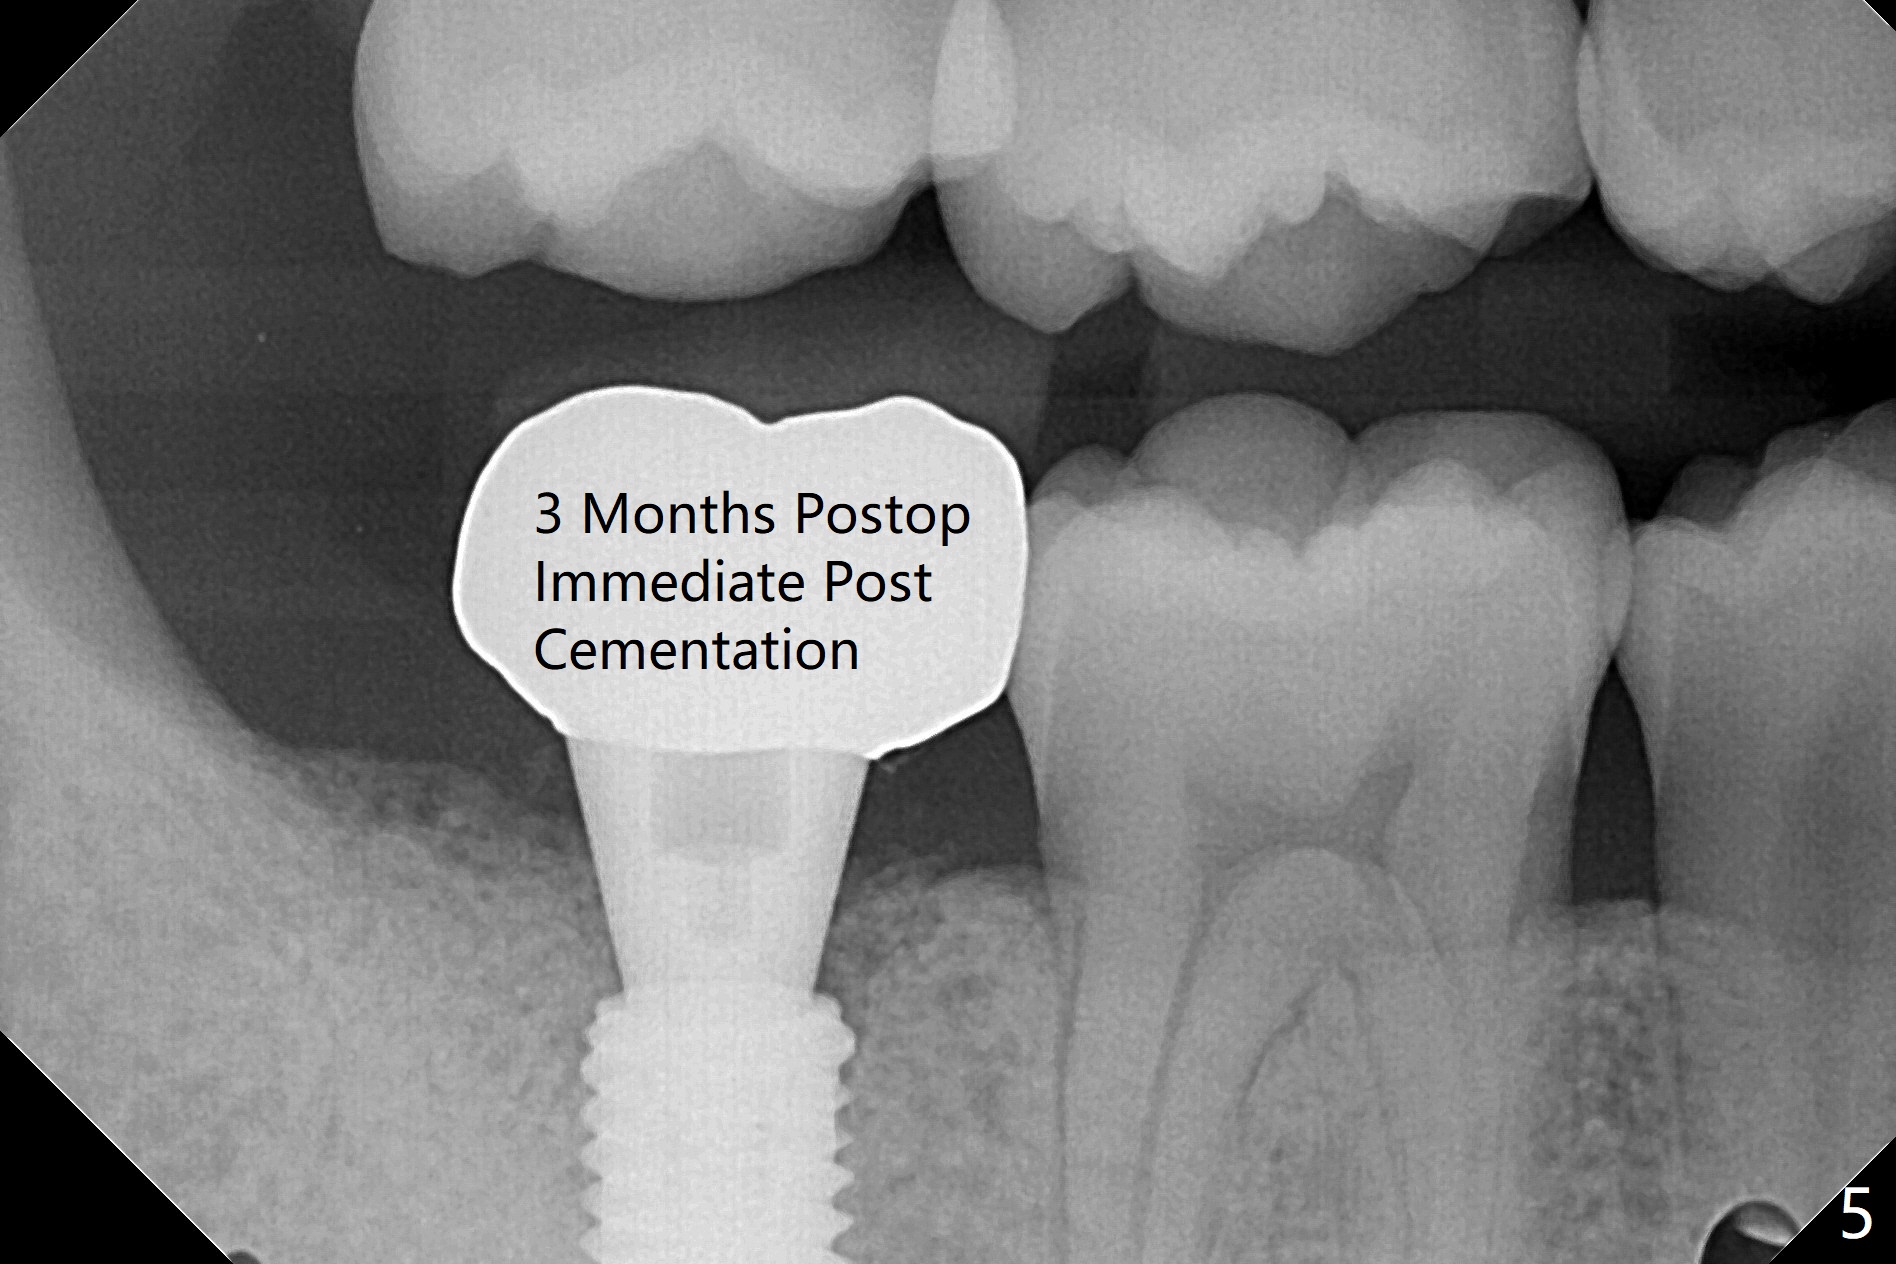

考虑到31号牙严重骨质吸收尤其是远中窝根尖(图一:*),实验室建议钻洞直径要比植体小三号(3.5毫米钻头;5.0毫米植体),其实行不通,使用4.0毫米钻头后,勉强植入4.5毫米报废植体(图一),阴差阳错:植体进入近中牙槽窝,植体四周都有骨壁包绕,包括远中:中隔(S)。最后为了使用5x11.5毫米植体,必须用4.5毫米钻头和5毫米皮质骨攻螺纹(到第三格,多3毫米,图二);放置基台好像没有就位。使用6毫米profile drill(好像去除舌侧中隔)后,手感基台就位,但是根尖片显示(图三)与图二没有区别(植体太粗,看不清楚植体与基台接触)。放置粘性骨粉后(图四),制作临时牙冠,放置PRF后,衬里多次增加固定和与牙龈密合度。术后医嘱包括手术区不使用水牙线。术后一周复诊询问骨粉游出问题。如果第二下磨牙种植能够进入近中窝,不必使用导板,4.5毫米足够,X光片观察基台就位也容易。术后三个月骨粉好像转变成正常骨质(图五,六, 30 Ncm)。